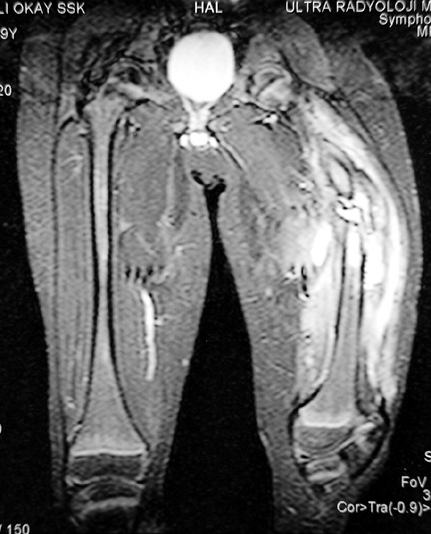

Chronic osteomyelitis leads to necrosis of bone and soft tissues. Dead bone is a nidus which hosts pathogenous microorganisms. Defence mechanisms of the host is usually not in optimum condition to deal with microorganisms. Antibiotics can’t reach the infection site because blood flow is disrupted. For these reasons, dead bone has to be completely removed by radical debridement.

Appropriate radical debridement necessitates excision of all necrotic bone and soft tissues, and frequently causes instability at the involved extremity. The remaining bone and soft tissue defect has to be fixed and reconstructed. The distraction osteogenesis method of Ilizarov is used successfully for achievement of union, correction of the deformity, elimination of limb length inequality and reconstruction of segmental bone defects.

The duration of external fixation (external fixation index) depends on the amount of distraction required, and the extremity is prone to complications during this period. After the distraction phase is completed, the external fixator remains in place during the consolidation phase, which lasts twice as long as the distraction phase; but this period is hardly tolerated. If the external fixator is removed before sufficient consolidation is achieved, fractures, deformity and shortness will be the result. In our department, ‘lenghthening over nail’ method is used in order to decrease the external fixation index and increase patient comfort and activity level. In this method, the intramedullary nail is statically locked after the completion of the distraction phase, and external fixator is removed. The extremity is stabilized by the intramedullary nail during consolidation phase. In this way, complications due to long external fixation index or early removal of the external fixator are avoided.